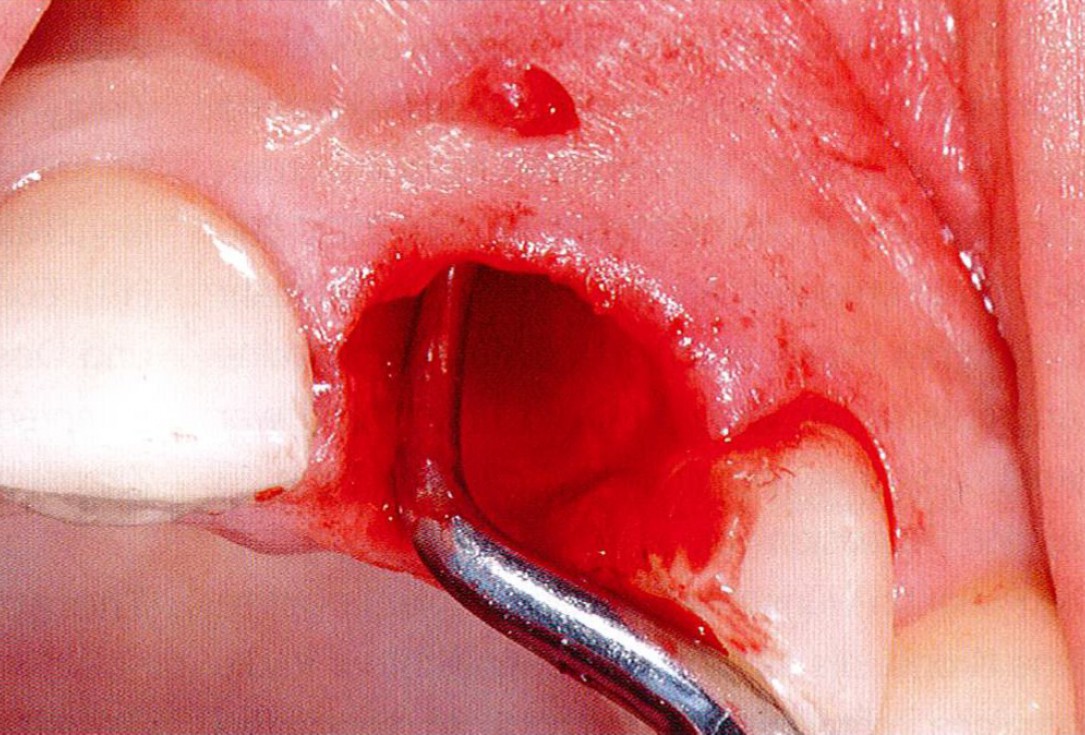

1/18 - Longitudinal fracture on the root resected tooth 21 with visible buccal fistulaGBR together with soft tissue augmentation with mucoderm® and maxresorb® - Dr. S. Scherg